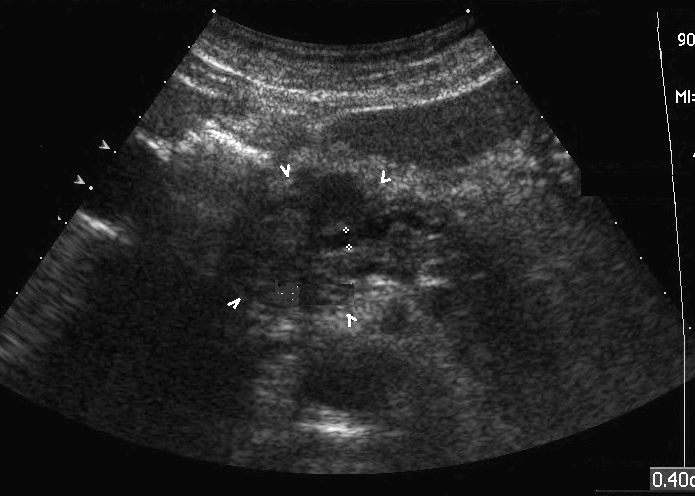

Echo-endoscopie :

Technique de choix pour recherche et diagnostic

des tumeurs de diametre a moindre 2mm du pancreas . Image

echographique recevoir est une nodule a bord irregulier ,

flou et hypoechogene . Technique est inconvenient par doit

etre realise sous anesthesie generale